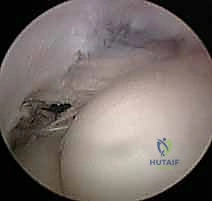

* يتم استئصال النسيج الندبي والتنكسي الرمادي اللون بدقة متناهية (Excision of angiofibroblastic tissue).

* تقشير العظم (Decortication): يقوم الدكتور هطيف بعمل ثقوب دقيقة جداً في عظم اللقيمة الوحشية. هذا الإجراء الحيوي يسمح بخروج الخلايا الجذعية وعوامل النمو من نخاع العظم إلى منطقة الوتر، مما يحفز بناء نسيج وتري جديد وقوي.

2. جراحة الكوع بالمنظار (Arthroscopic Tennis Elbow Release)

باعتباره رائداً في جراحة مناظير المفاصل في اليمن، يقدم الدكتور هطيف خيار الجراحة بالمنظار (بتقنية 4K عالية الدقة).